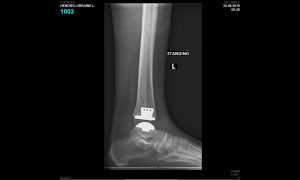

This is a graphic illustration of the Salto ankle prosthesis on the left and XR of the prosthesis in the ankle following the surgery for a patient with traumatic arthritis.